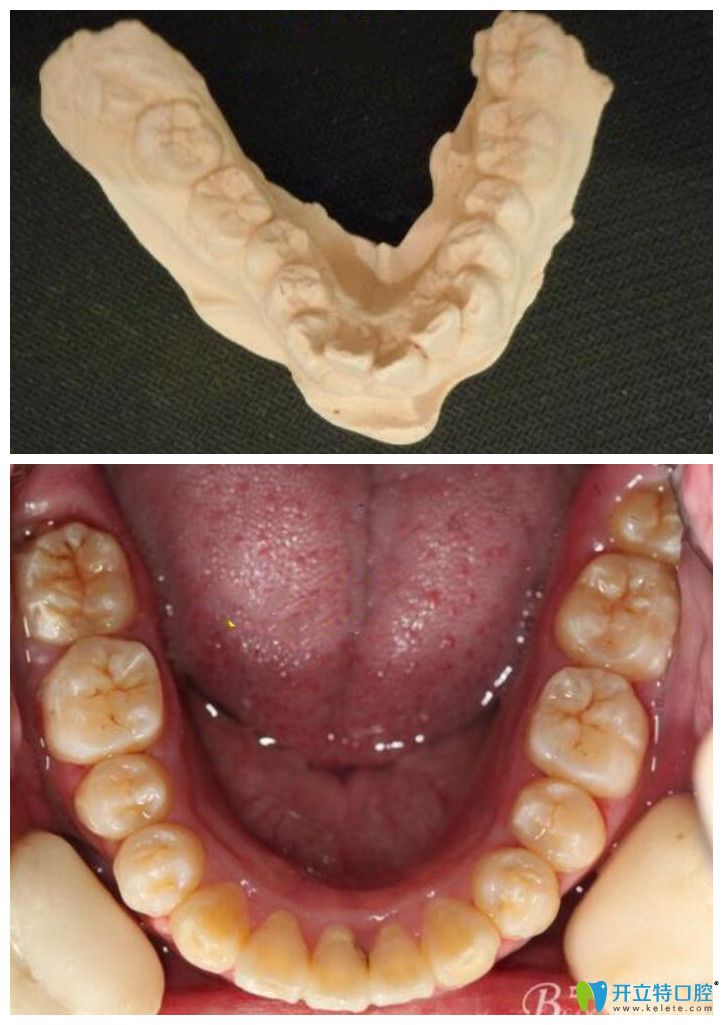

▲牙弓狹窄采用擴弓+金屬鋼絲矯正案例

牙弓狹窄臨床上常見到的一種表現(xiàn),通常指上頜第·一磨牙間的距離<33mm是狹窄的,具體表現(xiàn)為上下前面牙齒向前凸,后面大牙齒往舌側(cè)就是往內(nèi)側(cè)移動,導(dǎo)致上下牙齒排列的弓形變的長窄。